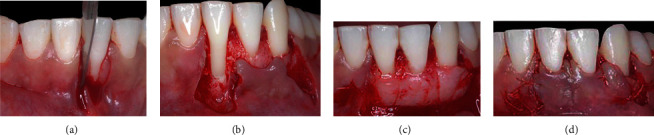

After supragingival periodontal therapy, the protrusive occlusal interference in #41 tooth was subsequently adjusted to balance the contacts and improve the distribution of forces. To adjust this, occlusal contact markings were made at maximum habitual intercuspation, protrusion, and right and left laterality. For selective wear, spherical and tapered diamond (KG Sorensen, Cotia, São Paulo, SP, Brazil) tips were used, in addition to abrasive rubber, discs, and polishing paste (TDV Dental, Pomerode SC, Brazil), until the establishment of balanced contacts during mandibular movements were established, in order to maintain a mutually protected occlusion. Two weeks after the occlusal adjustment, periodontal surgical treatment was performed using the LPF + SCTG technique (T.M.M.), as previously described (Figure 3).

Figure 3.

Case 1. (a) Vertical internal bevel incision extending into alveolar mucosa and external bevel incision along distal gingival margin of the recession defect and extending into alveolar mucosa. (b) Deepithelialized area after intrasulcular incision. (c) Flap of mix thickness. (d) Connective tissue graft positioned and stabilized. (e) Laterally positioned flap without tension and secured with sutures on recipient site.

The CTG, with an average thickness of 1 mm, was removed from the palate, in the region between the first maxillary premolar and the first molar, using the D-FGG technique [19]. The CTG extended high enough into the mesiodistal direction, to cover teeth 41 and 42, high to cover the exposed root surface and remain within the tunnel created under the initial mesial incision of 41 tooth, in order to be covered by LPF later (Figure 3).